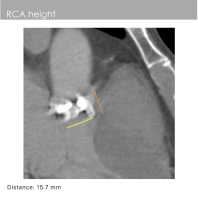

右冠开口高度:15.7mm

主动脉窦部钙化严重